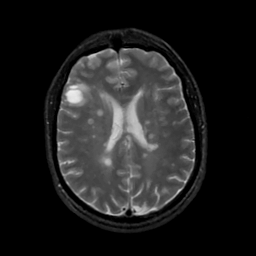

MR Study #6, March 17, 1991 -- Slice #31